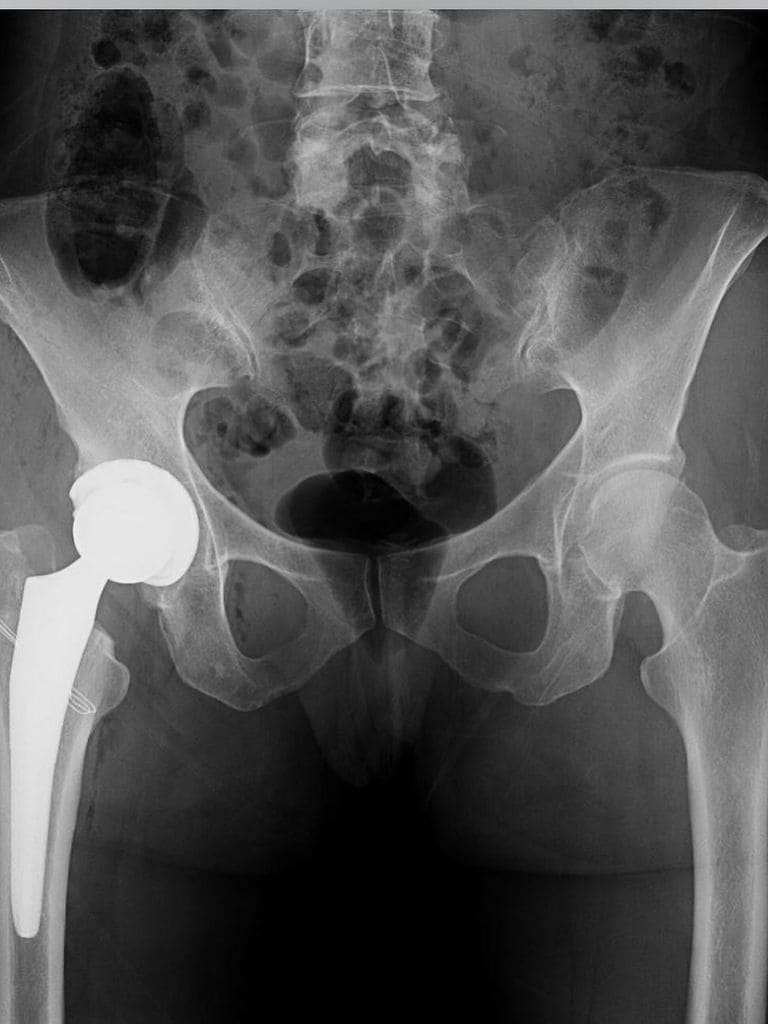

“Estas fotos os la hice para compartir lo que no siempre se muestra.” Así explicaba su decisión de mostrar una parte más íntima y poco habitual de su vida. La modelo, muy activa en redes sociales, ha querido hablar con naturalidad sobre el motivo de su ingreso. “Hace unos días me operaron por unas lesiones debidas a una artrosis severa en la cadera. Me han puesto una prótesis de titanio. Era necesario. El dolor ya no me permitía seguir con mi ritmo habitual. Este mes de septiembre ha sido especialmente retador.”

A sus 49 años, Eugenia Silva sigue siendo uno de los rostros más emblemáticos del mundo de la moda española. Licenciada en Derecho, madre de dos hijos y con una carrera internacional consolidada, la modelo ha sabido combinar su faceta profesional con su papel de empresaria y madre. La artrosis severa de cadera, una dolencia degenerativa que provoca dolor y limita la movilidad, suele requerir cirugía cuando los tratamientos ya no alivian los síntomas. En el caso de Eugenia, la colocación de una prótesis de titanio ha sido la solución necesaria para recuperar la calidad de vida y poder volver, poco a poco, a su actividad habitual.

La intervención, realizada por el Doctor Luis Novoa y su equipo en Clínica CEMTRO. “Gracias por estar cerca también en estos momentos y gracias al Dr. Novoa, la Dra. Ruiz y todo el equipo de la clínica”, escribió como agradecimiento.